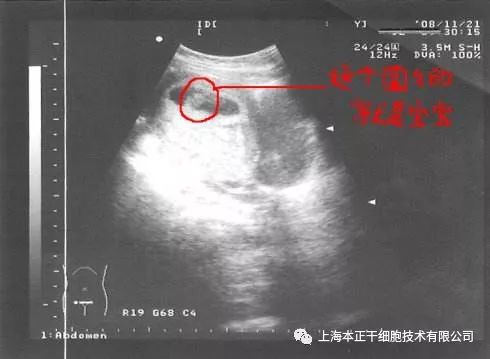

干细胞治疗方案:对患者刮宫后,在产生引导下用注射器经宫底及宫腔内注射入患者干细胞悬液,术后辅以阿司匹林和周期性激素治疗。超声检查结果显示患者术后子宫内膜再生较好,并且,患者通过体外受精(in vitro fertilization,IVF)成功怀孕,随访至妊娠第八周胎儿生长良好。

图1:宫腔镜检查-子宫内膜粘连